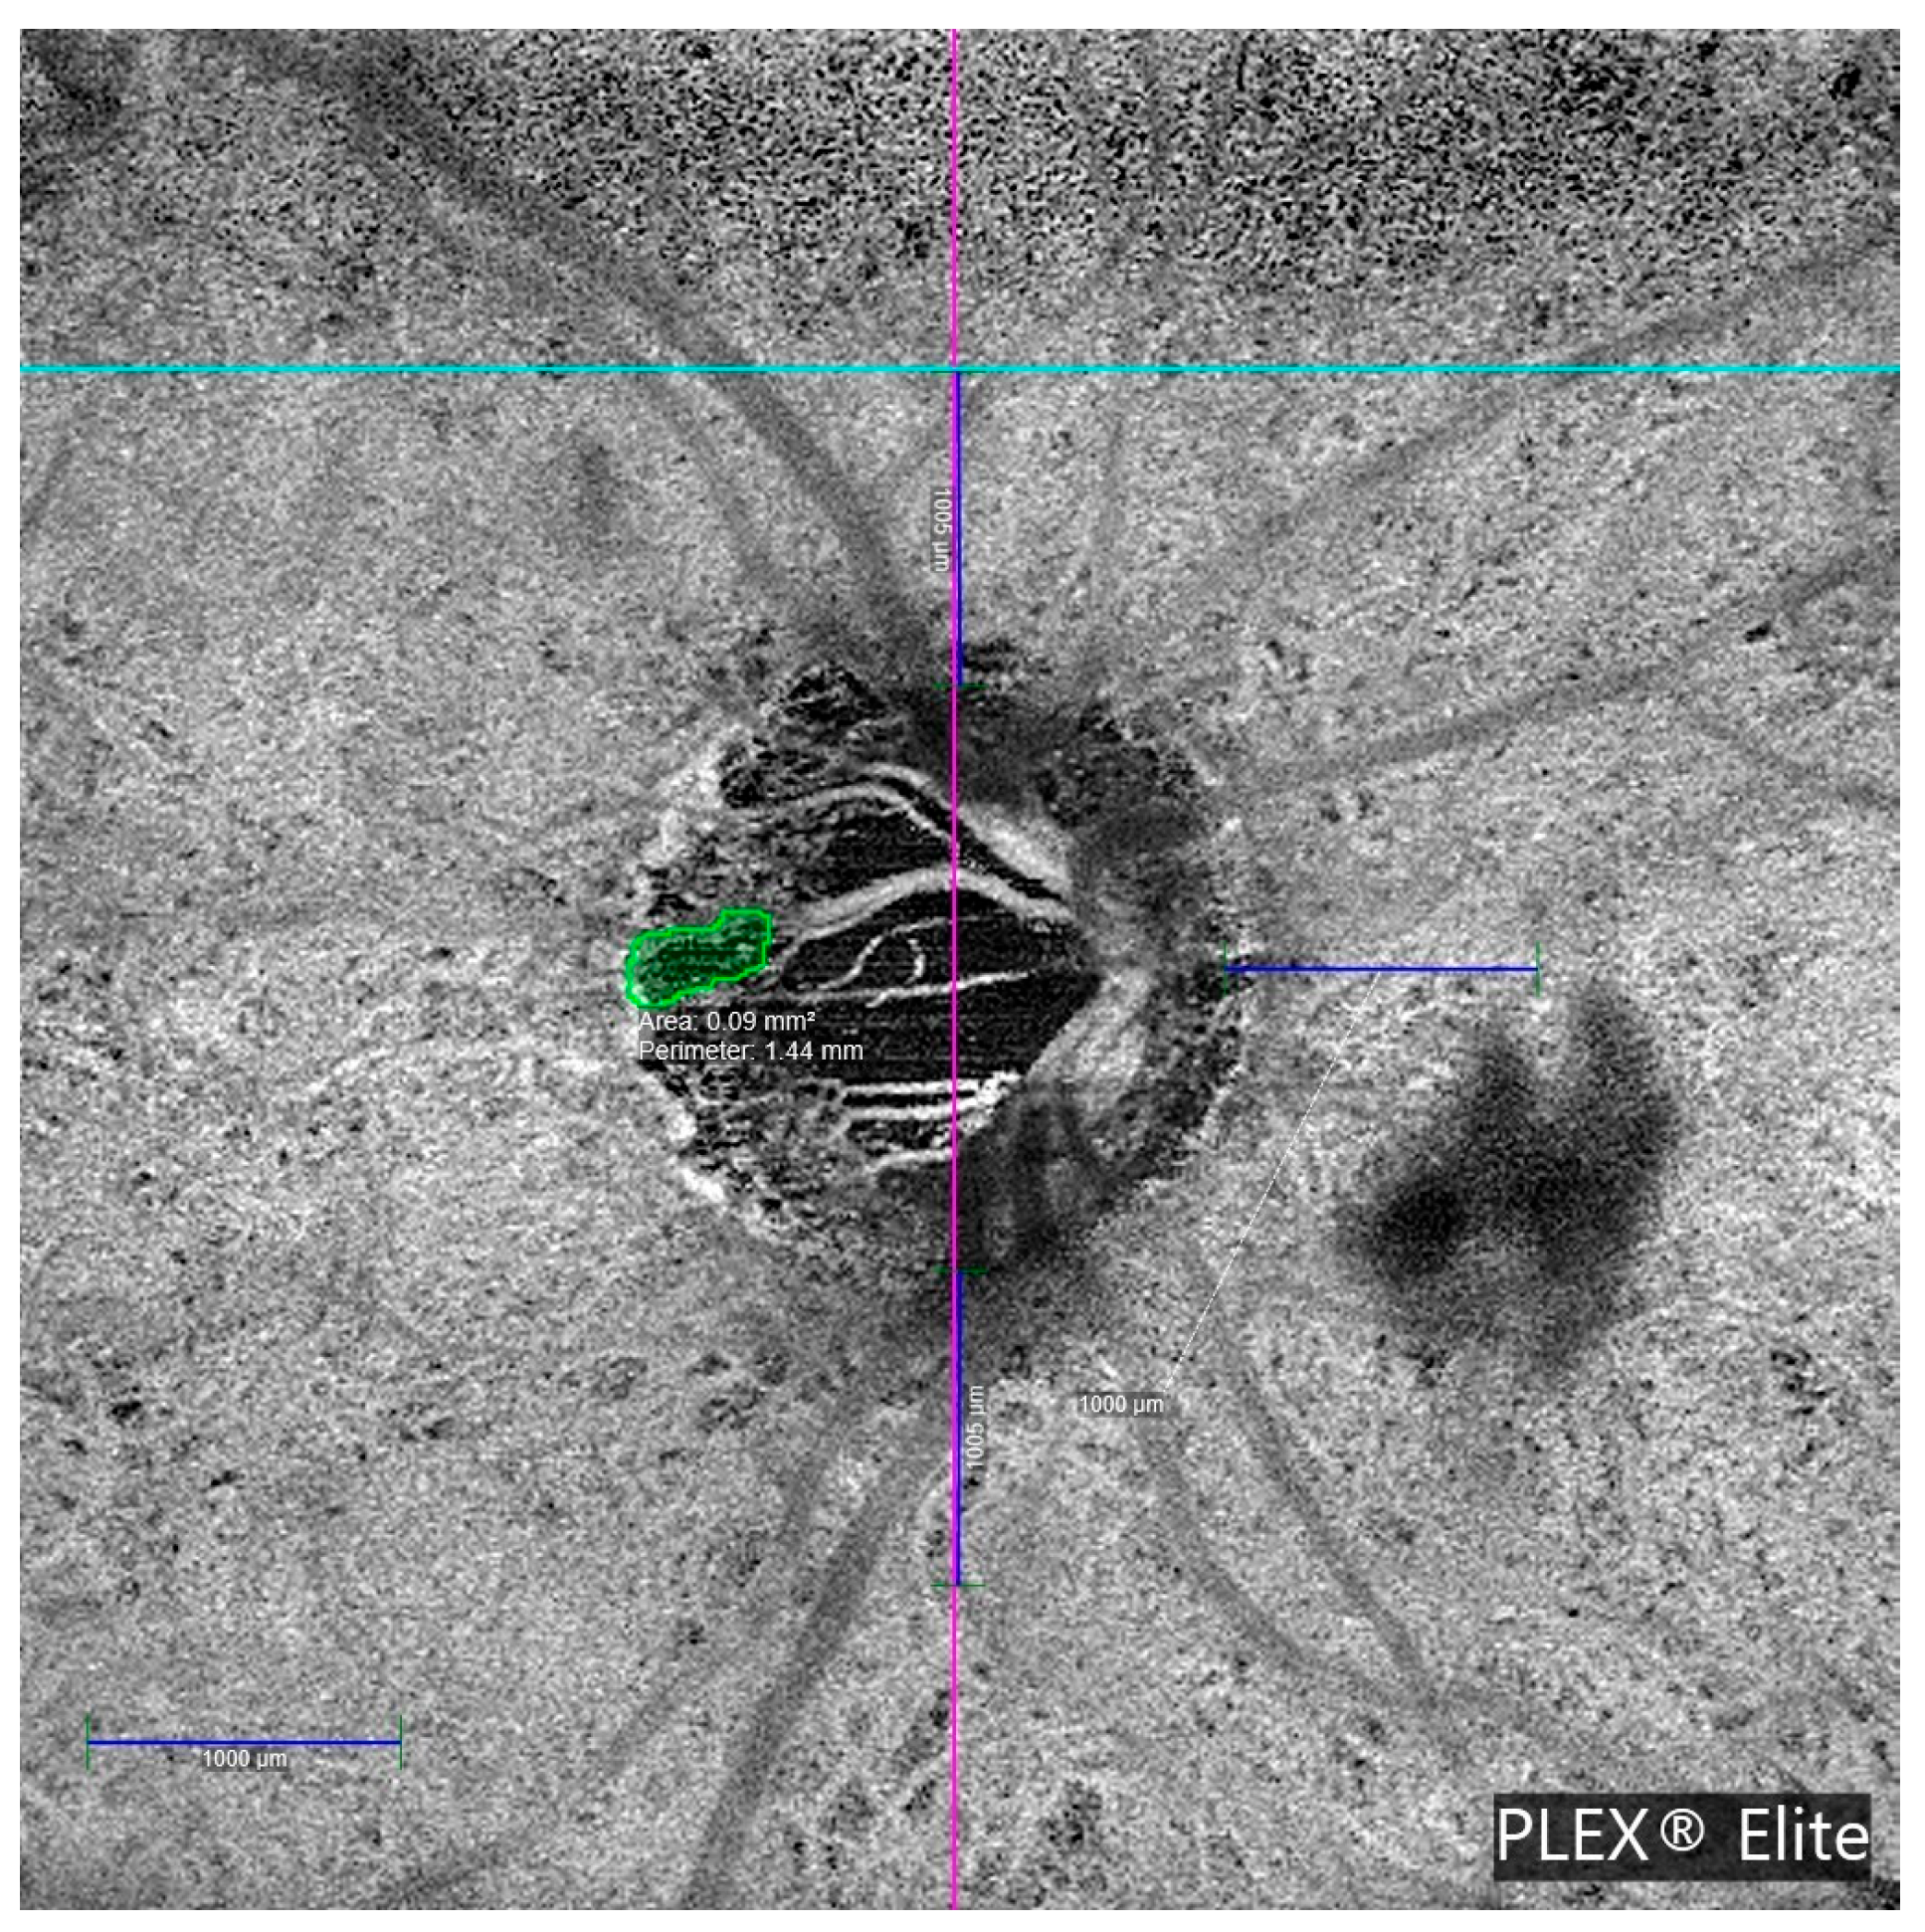

MvD was detected in 7 of the 29 OAG patients, with bilateral involvement in three cases, resulting in 10 affected eyes. No MvD was observed in healthy controls. Both examiners agreed on the determination of the presence of MvD in all cases. The interexaminer ICC for the MvD perimeter measurement was 0.979 (95% CI: 0.917–0.995; p < 0.001). Table 3 details the clinical characteristics of glaucoma patients with MvD. Most MvDs were located in deep vascular layers, specifically, the choriocapillaris and choroid. Only 2 of the 10 cases showed MvD in the superficial vascular plexus. All MvD-positive eyes exhibited β-PPA. Figure 4 illustrates a representative en face OCTA image showing MvD in a glaucomatous eye.

Figure 4. Optical coherence tomography angiography (OCTA) en face image acquired using the PLEX® Elite 9000 system, showing a circular region of interest within the peripapillary area. Cyan and magenta crosshairs intersect at the center of the optic nerve head, providing spatial reference. Quantitative measurements include the total microvascular dropout (MvD) area (0.09 mm2) and perimeter (1.44 mm). Scale bars of 1000 µm are shown for calibration.